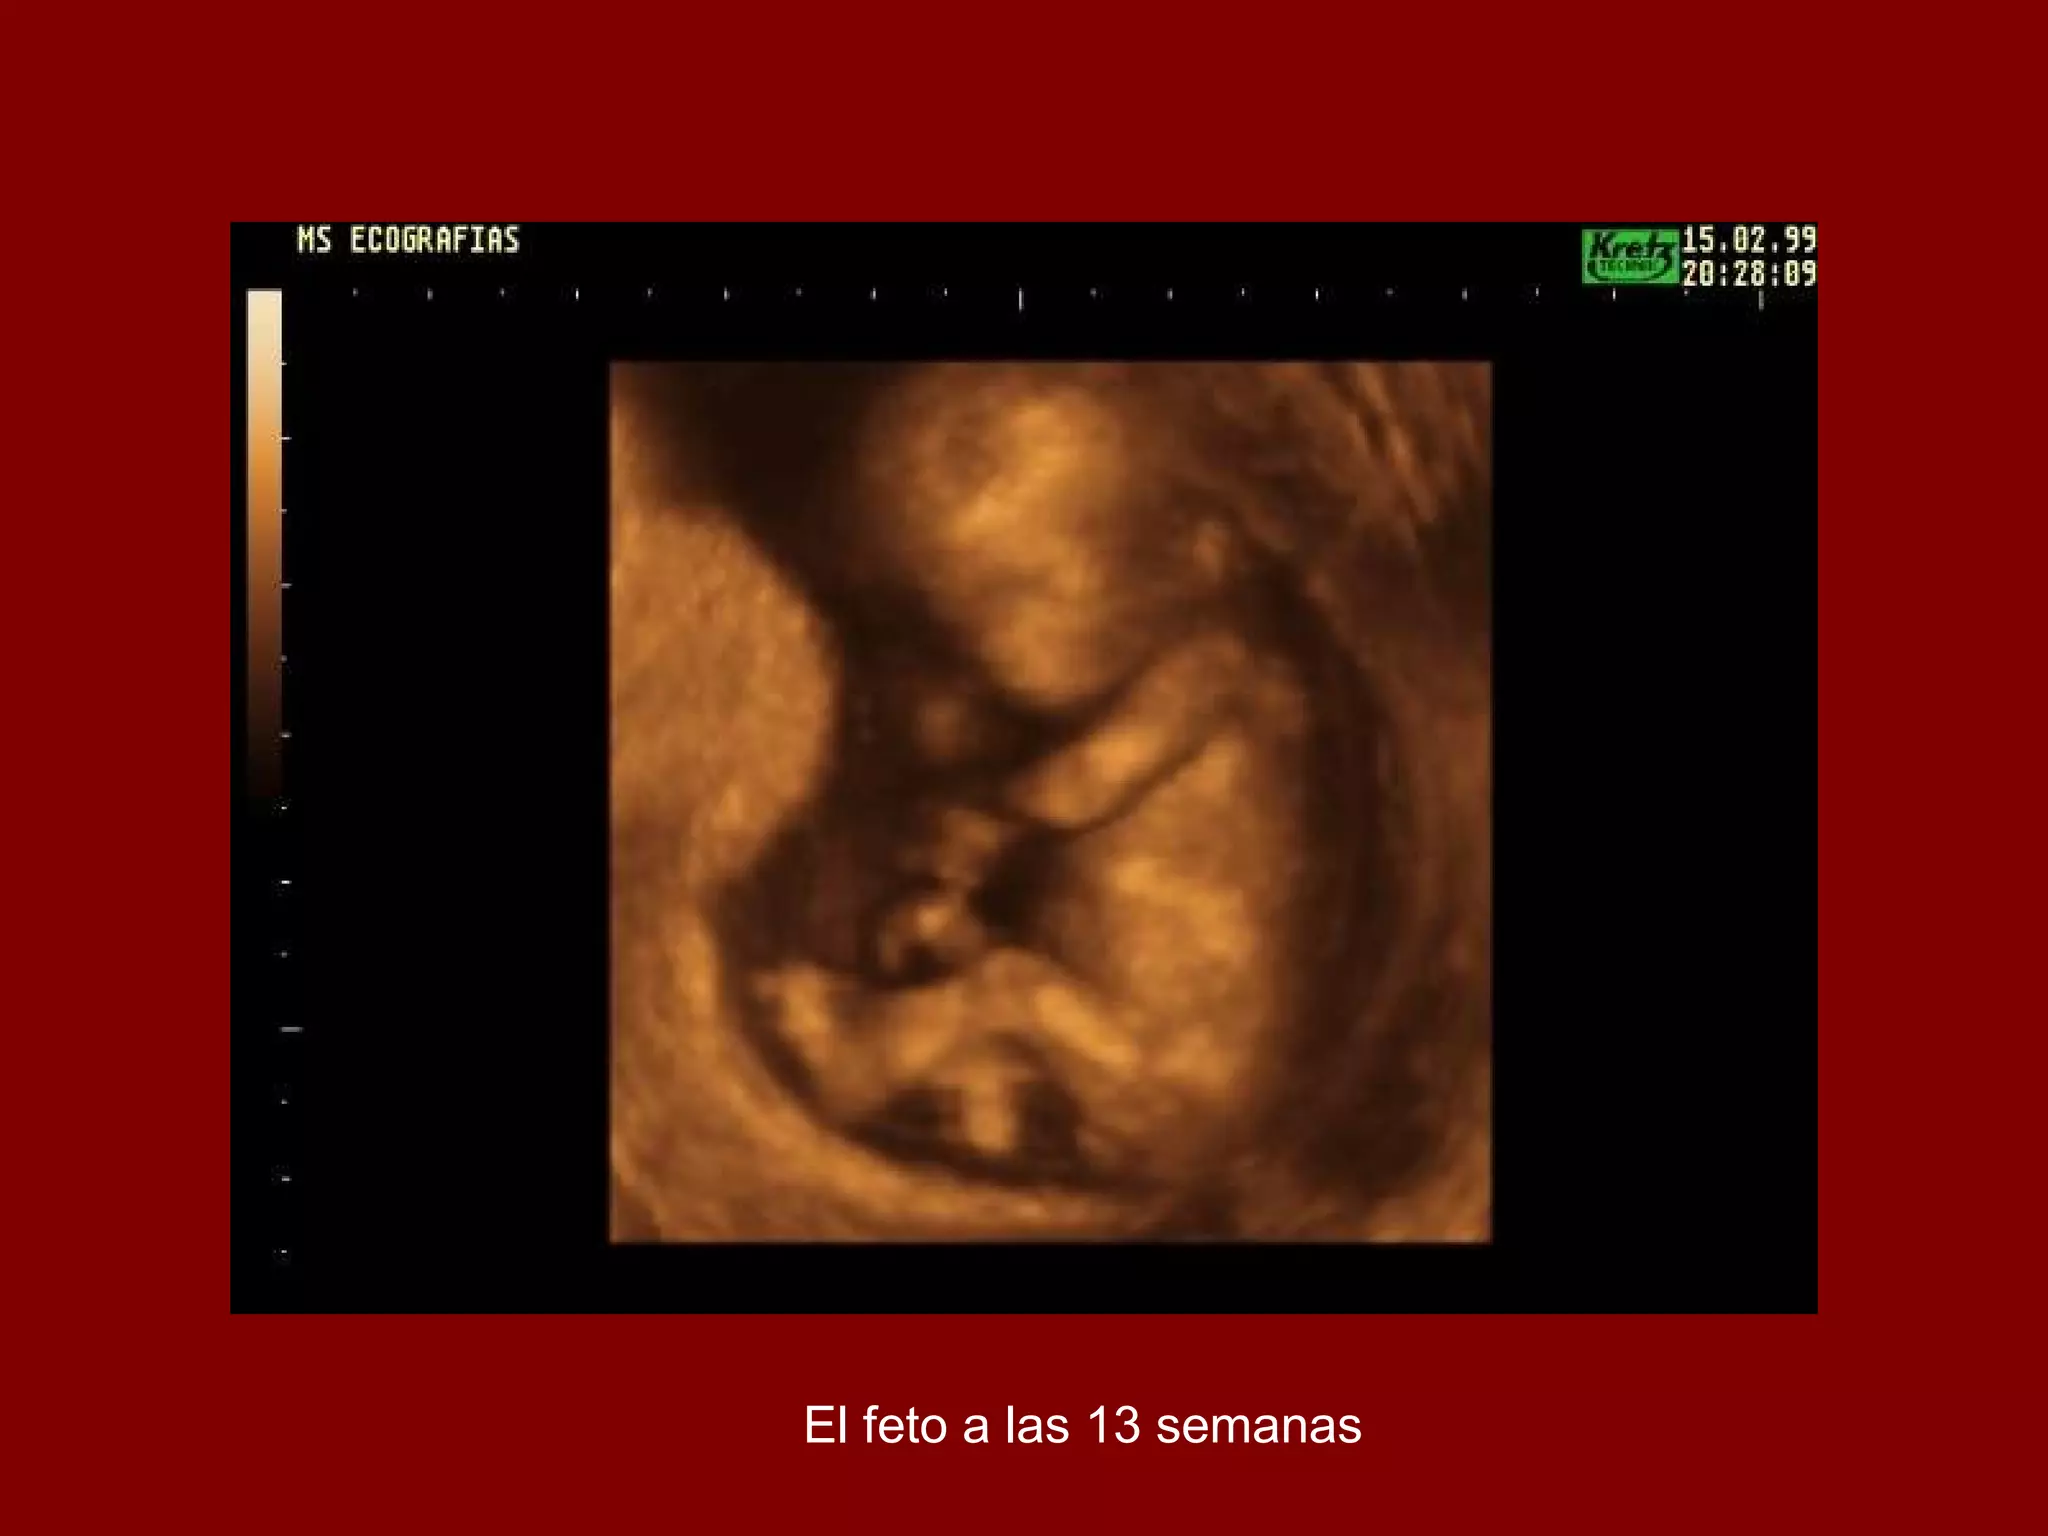

El documento describe el desarrollo de un feto desde las 9 semanas hasta los 36 años según ecografías 3D. Muestra la progresión desde apenas distinguir algo a las 9 semanas hasta ver al feto completamente formado a los 30-36 años. Termina diciendo que "se jodió el feto".